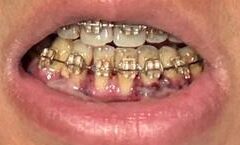

歯肉移植手術2回目(手術方式:ADM、術部:左下2番・3番と右下2番・3番、手術時間2時間)

・1時間後:術部に若干の痛みはあるが、1回目の手術より体調は楽。

・3時間後:昼食を食べることができた。熱いものは避けるよう言われているので、常温で柔らかいものを奥歯で噛むように心がけた。上顎の手術を実施していないので食べやすい。

・19時間後:痛みもなく、食事も柔らかくて熱くなければ普通に食べられた。歯磨きは怖いので、下の歯は術部に触れないよう先端の細いブラシで慎重に磨いた。

・89時間後:右下3番の縫合が外れ、歯間ブラシに絡まって引っ張ってしまい、前日の夜に軽い出血があった。

・154時間後:右下3番の外れた縫合部を再縫合してもらった。歯茎の付き方は右下の方が左下よりも良く、引き続き来週の検査で状態を確認する。

左(上)から:術後3時間後、術後19時間後、34時間後、58時間後、65時間後、89時間後、114時間後、154時間後